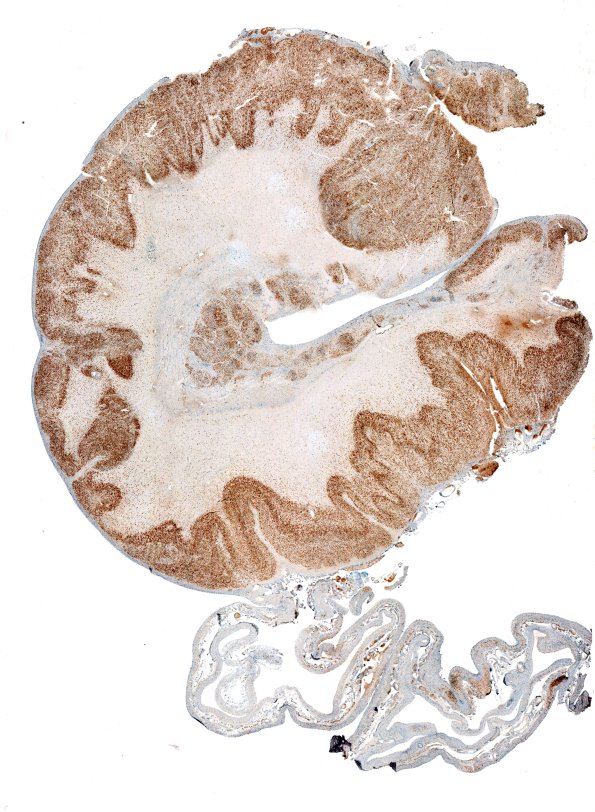

Washington University Experience | DEVELOPMENTAL MALFORMATIONS | Encephalocele | 9D Encephalocoele (Case 9) NeuN whole mount 2

The abnormal patterns and locations of neurons are highlighted on sections stained immunohistochemically for the neuronal marker NeuN. (NeuN IHC) ---- Not shown: The membranous tissue attached to the skin shows a layer of glial tissue on only one side, the other surface covered by an exceedingly thin stratified squamous epithelium.